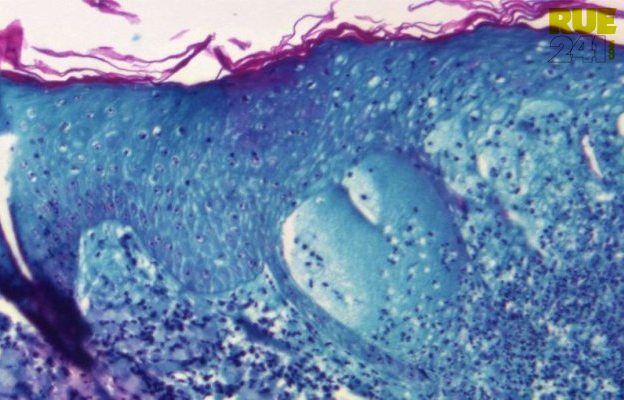

L’OMS classe la variole du singe en urgence de santé publique internationale

La variole du singe a été classée en urgence de santé publique de portée internationale par le Directeur général de l’Organisation mondiale de la Santé (OMS) ce samedi.